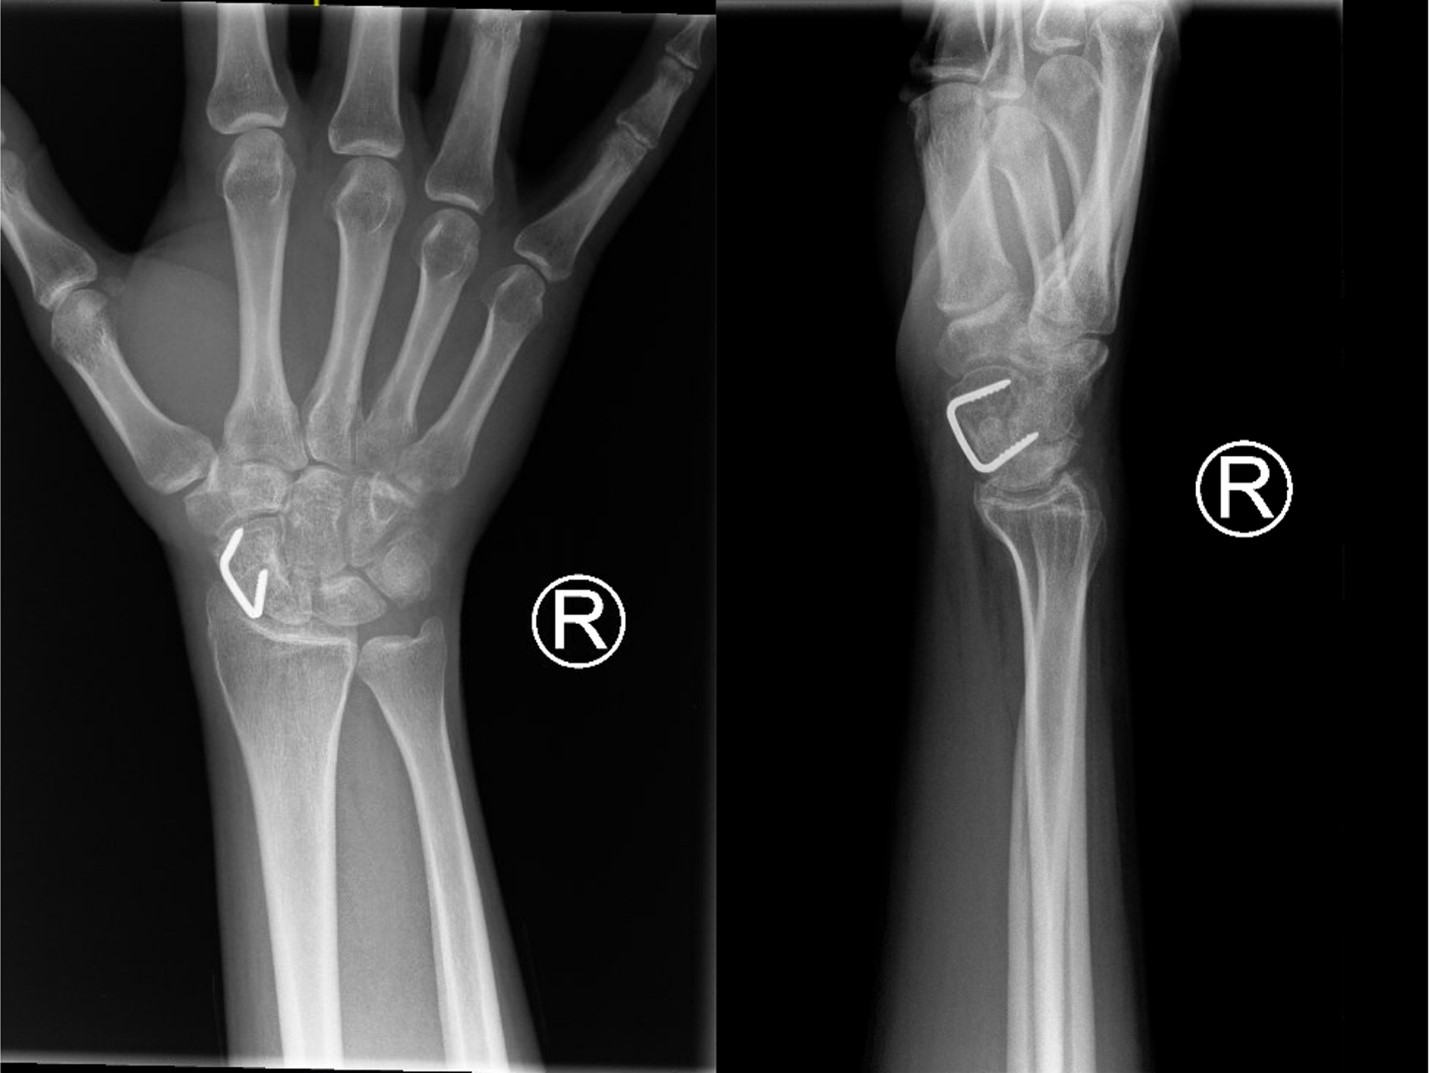

Following Institutional Review Board approval, all patients who underwent a repair of the scaphoid with open reduction and external fixation by 1 of 4 board-certified hand surgeons between 2010 and 2020 were identified by Current Procedural Terminology (CPT) codes 25440 and 25628. Subsequent chart review was performed to determine fracture location, union status, and surgical fixation technique. Patients who had surgical fixation of a scaphoid waist fracture with either a single nitinol compression staple via a volar approach (Figure 1) or a single headless compression screw were included (Figure 2). They were then stratified into 2 groups by fixation device that was based on surgeon preference. Patients with a staple were required to have undergone a volar approach as described by Congiusta et al.21 Exclusion criteria included prior intervention, pathologic fracture, less than 12 weeks follow-up, and less than 4 weeks between injury and surgery. Once identified, a full chart review was performed to collect data for statistical analysis.

Figure 2. Fixation with a single headless compression screw.